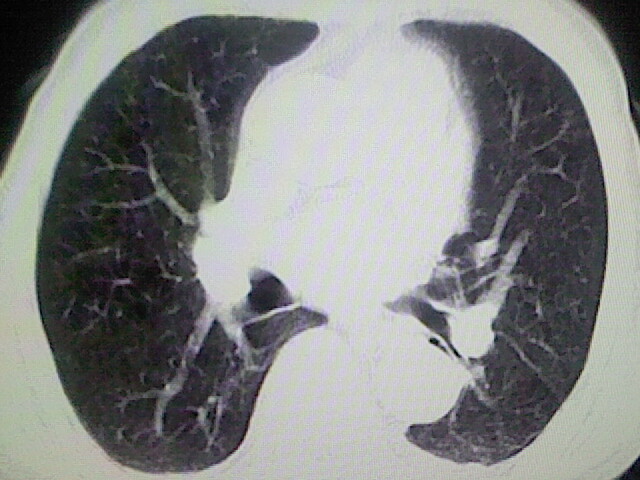

以下是引用zsl6918在2008-8-28 16:49:00的发言:[br]双肺炎性病灶,食管狭窄估计与心房增大压迫所致。

以下是引用xulianj在2008-8-28 20:36:00的发言:[br]慢支肺气肿伴感染,右上肺陈旧性结核;食道建议胃镜检查。

以下是引用wqs571018在2008-8-28 21:18:00的发言:[br]慢支继发感染,右上肺陈旧性结核;食道建议胃镜检查。